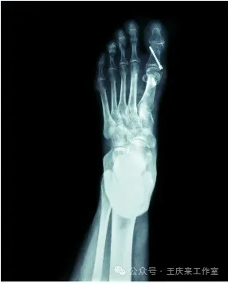

拇外翻,又稱“大腳骨”,是指大腳趾向外傾斜超過了正常生理范圍,通常伴有第一跖骨頭內(nèi)側(cè)的骨贅形成。它的成因多種多樣,遺傳、穿著不合適的鞋子(尤其是高跟鞋)、足部韌帶松弛、長(zhǎng)期站立或行走等都是誘發(fā)因素。初期可能僅表現(xiàn)為外觀異常,隨著病情發(fā)展,可能會(huì)伴隨疼痛、紅腫、走路困難等癥狀。

手術(shù)治療:對(duì)于中重度拇外翻或保守治療無效者,可能需要通過手術(shù)糾正拇趾位置。手術(shù)方式有許多種,主要目的是切除增生的骨贅,重建相關(guān)韌帶結(jié)構(gòu),以恢復(fù)正常步態(tài)和緩解疼痛。